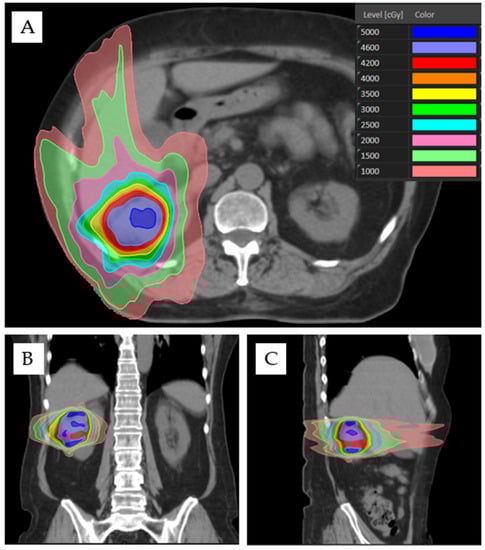

3.3. Treatment Setup, Design, and Delivery